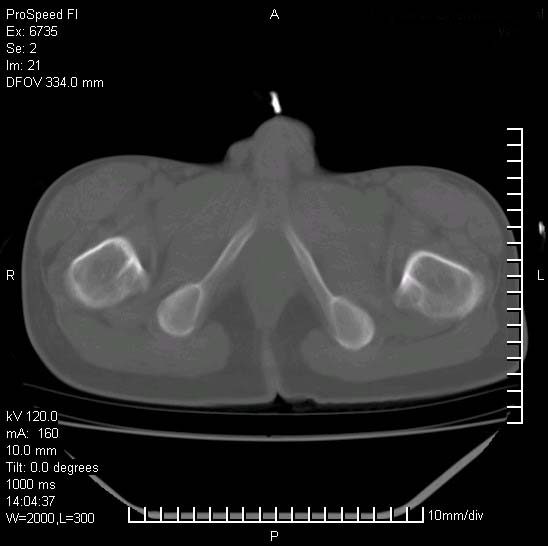

患者自诉胯部疼痛两年余,在当地服用中药,半月前至本院考虑骶髂关节结核,给予抗痨治疗。现发展至右下肢疼痛明显,活动受限,以膝关节处明显,拍膝关节平片无明显异常。

两侧骶骼关节改变,考虑强直性脊炎

左侧骶髂关节面限局性骨破坏,边缘硬化关节腔见钙化物;不出外tb

右侧骶髂关节也有类似改变,只是较左侧轻,首先考虑强直性脊柱炎,不除外结核,建议作hla-b27检查。

典型强脊炎改变,髋关节亦有累及

符合强直性脊柱炎表现。